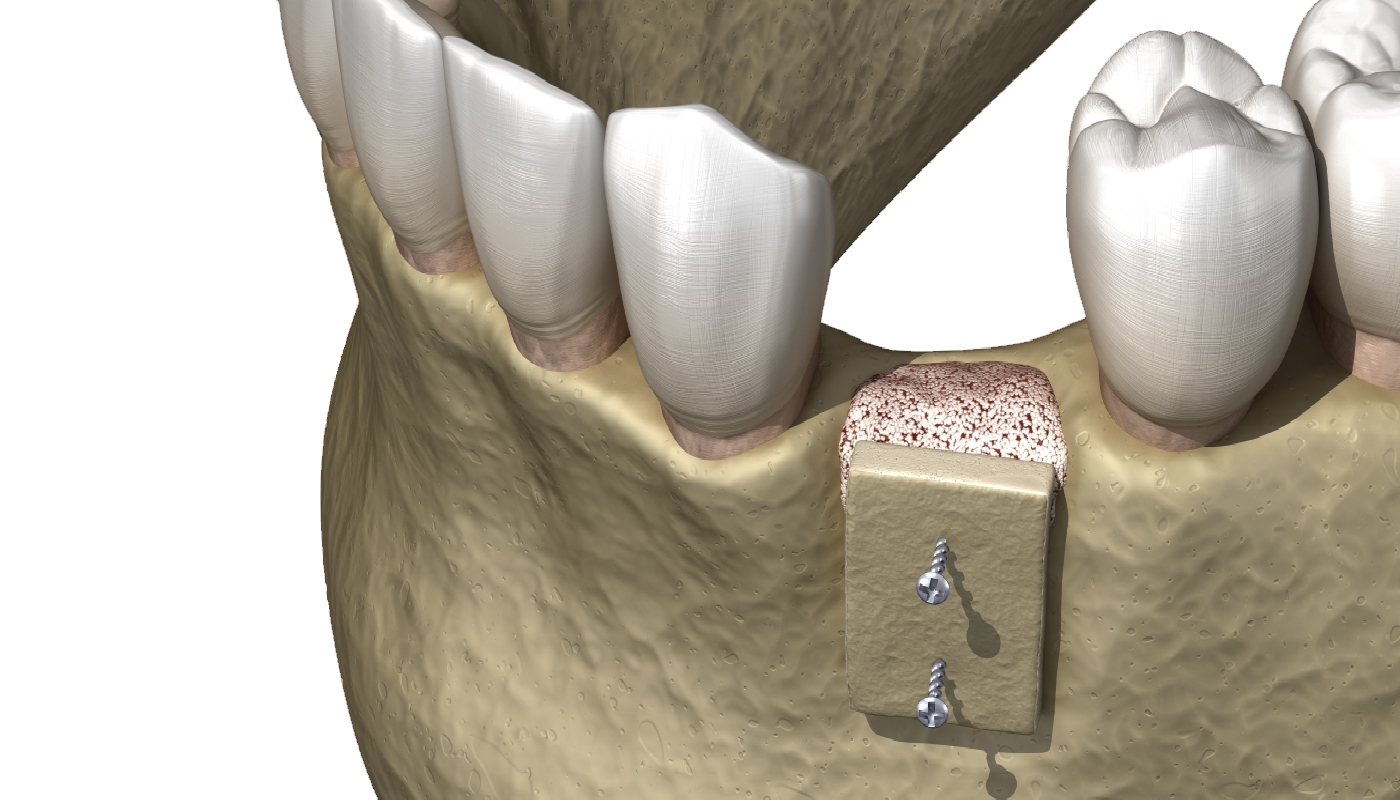

Rialzo del seno mascellare

Il rialzo del seno mascellare è un intervento di chirurgia ossea che permette di aumentare il volume dell’osso nella mascella superiore, per consentire...